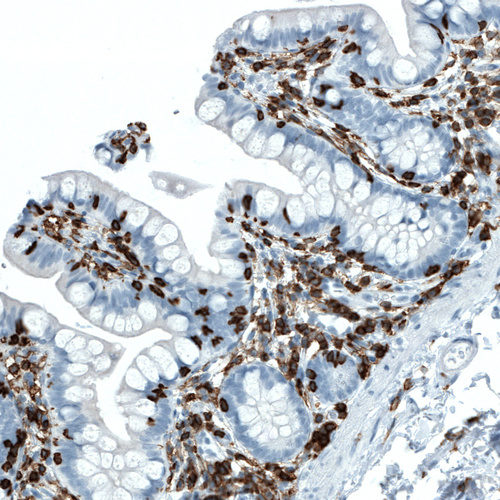

Immunohistochemistry analysis in human tonsil and skeletal muscle tissues using AMAb90518 antibody. Corresponding PTPRC RNA-seq data are presented for the same tissues.